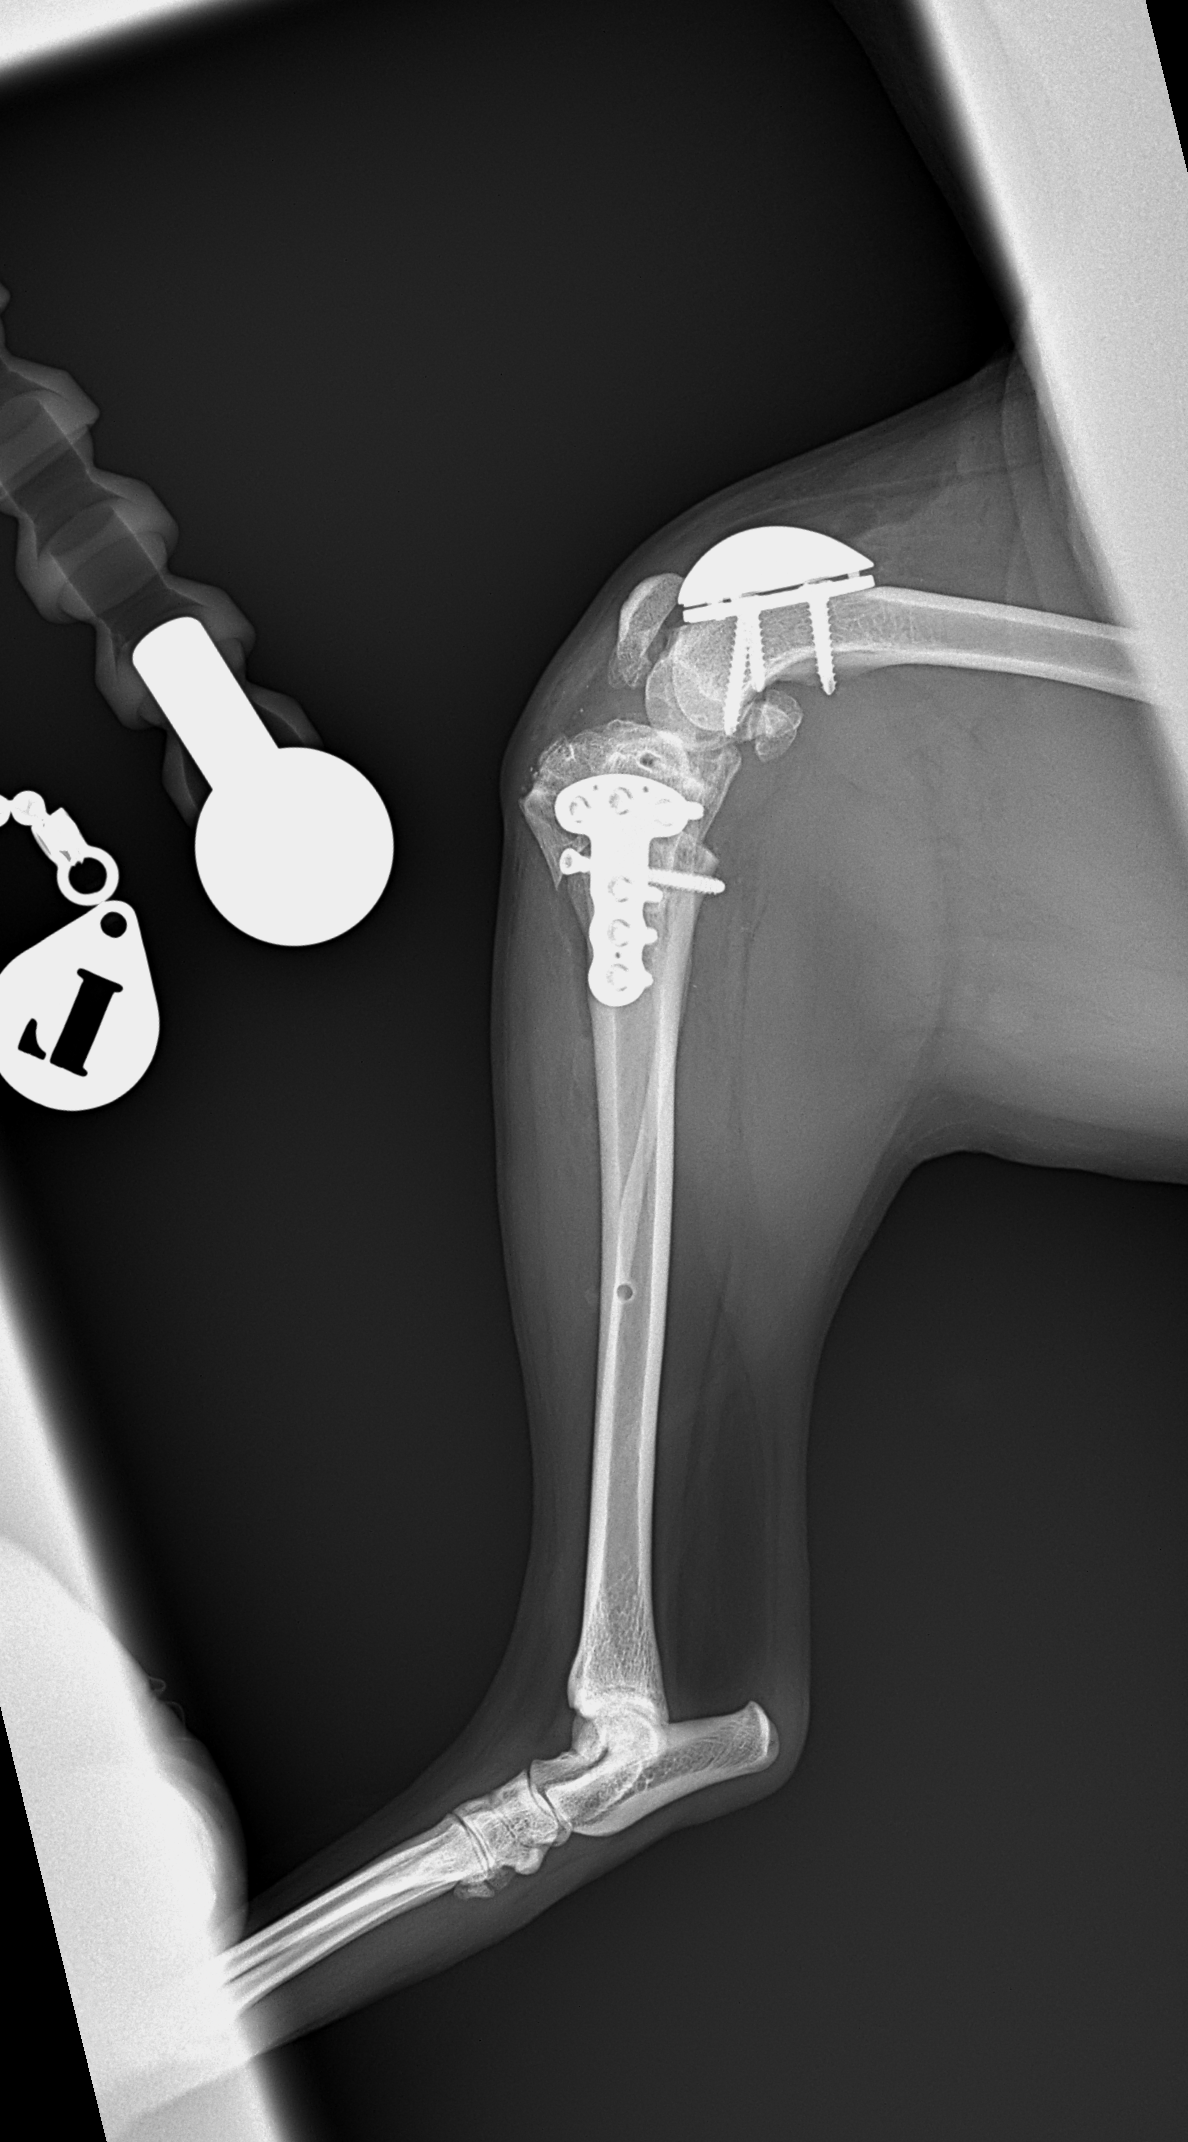

膝蓋骨内方脱臼+前十字靭帯断裂 PGR#21+CBLO #251

過去に膝蓋骨内方脱臼G4で手術を受けている患者さんが、急に跛行を呈するようになったとの事。関節炎が顕著であり、前十字靭帯断裂の併発も疑われます。ファットパッドサイン陽性、脛骨圧迫試験陽性、脛骨ピボット圧迫試験陰性でした。大腿骨滑車のリプレイスメントとCBLOで対応しました。